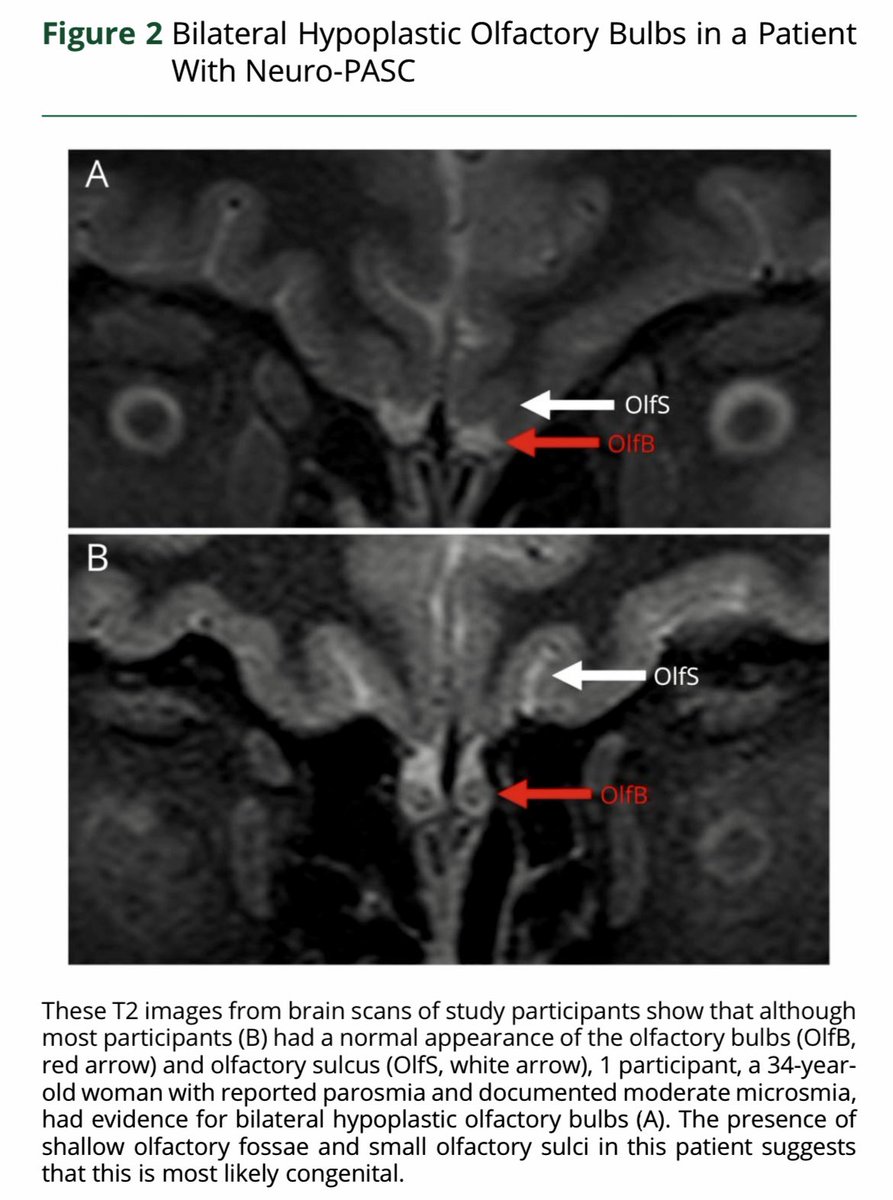

of Health (NIH) eingehend untersucht und wiesen Unterschiede in ihren Immunzellprofilen und autonomen Funktionsstörungen auf. Ein gemeinsames Merkmal ist die Beeinträchtigung des Gedächtnisses. Ein verringerter Geruchssinn war häufig, obwohl keiner der Patienten Image